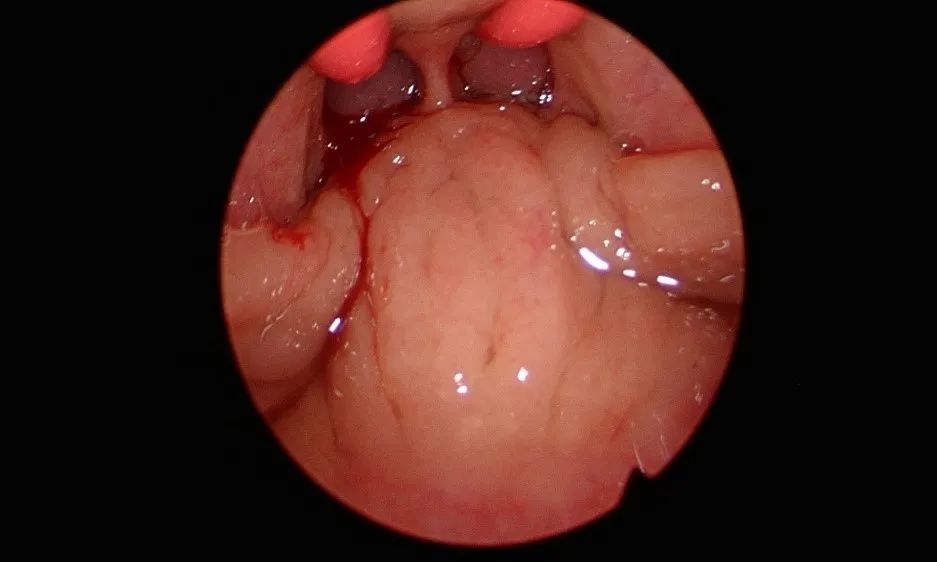

分泌性中耳炎做啥手术?

鼓室穿刺或置管,如伴有腺样体肥大,则行腺样体切除术。